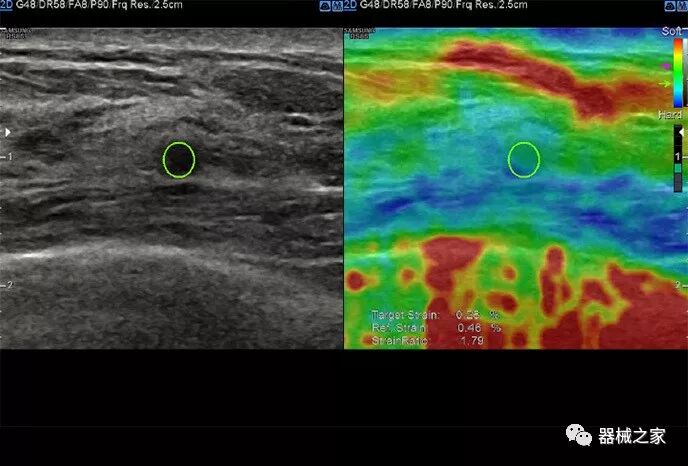

在几年前,超声波无法对小型慢流血管中的血流进行成像,但现在有少数供应商提供具有此功能的系统。该特征提供了另外一种检查病变以指示癌症或炎症的方法。其中一个是佳能Aplio 900 CV系统,它可以显示毛细血管中的血流量。日立的Arietta 65中程系统提供了一种可视化小血管的功能,可以更好地观察肾脏等器官的灌注情况。三星RS85还提供MV-Flow可视化慢流微血管结构。